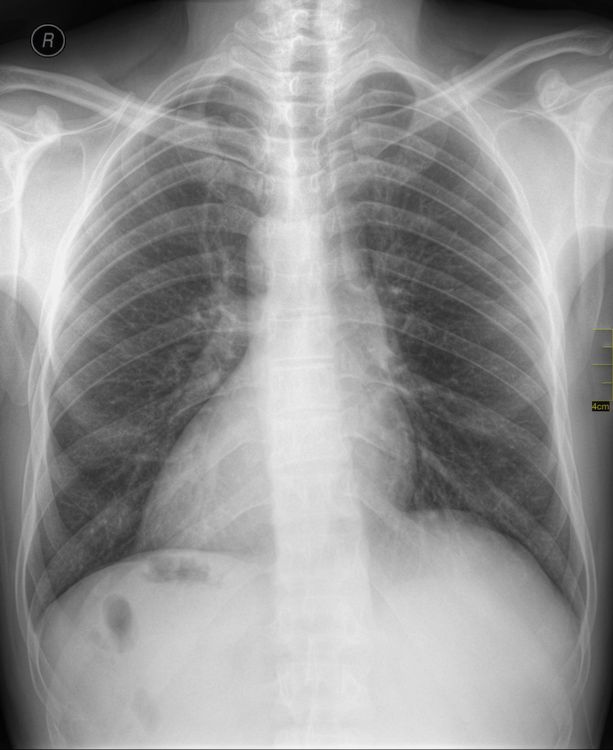

(हृदय उजव्या बाजूला)

जमालुद्दीन नावाचा हा माणूस नुकतंच पोटदुखीमुळे डॉक्टरांकडे आला होता. डॉक्टरांनी एक्स-रे काढल्यावर त्यांना धक्काच बसला. जमालुद्दीनच्या शरीरातील अवयव विरुद्ध बाजूला होते. त्याचं हृदय उजवीकडे आहे तर यकृत आणि पित्ताशय डाव्या बाजूला आहेत.

मंडळी, या प्रकाराला शास्त्रीय भाषेत Situs inversus म्हणतात. ही एक अवस्था असून यात माणसाच्या शरीरातील प्रमुख अवयव उलट्या दिशेत असतात. एकूण लोकसंख्येच्या अवघ्या ०.०१% एवढ्याच लोकांमध्ये ही अवस्था सापडते. बऱ्याचशा लोकांना आपल्या शरीरात असे उलटे अवयव आहेत हे माहितीच नसतं. त्याचा शरीरावर विपरीत परिणाम देखील होत नसतो.